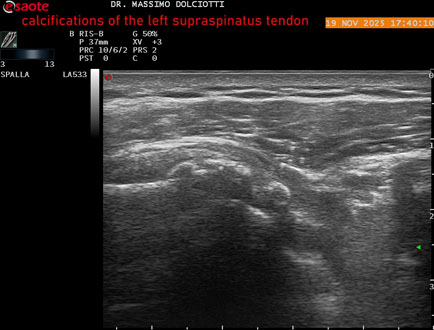

Data inserimento: 21/11/2025

Ecografia del: 19/11/2025

Strumento: Esaote MyLab Eight

Sonda: Lineare Multifrequenza 3-13 MHz

Età Paziente: M 52 anni

Motivazione dell'esame: dolore alla spalla sinistra che peggiora con il freddo.

Commento all'esame: le immagini ed il video documentano il tendine sovraspinato sinistro disomogeneo per evidenza, in sede prossimale e mediale, di immagini iperecogene multiple, delle dimensioni di 5,8 mm - 6,1 mm - 4,6 mm da ricondurre a calcificazioni.

Conclusioni: calcificazioni del tendine sovraspinato sinistro (calcifications of the left supraspinatus tendon).